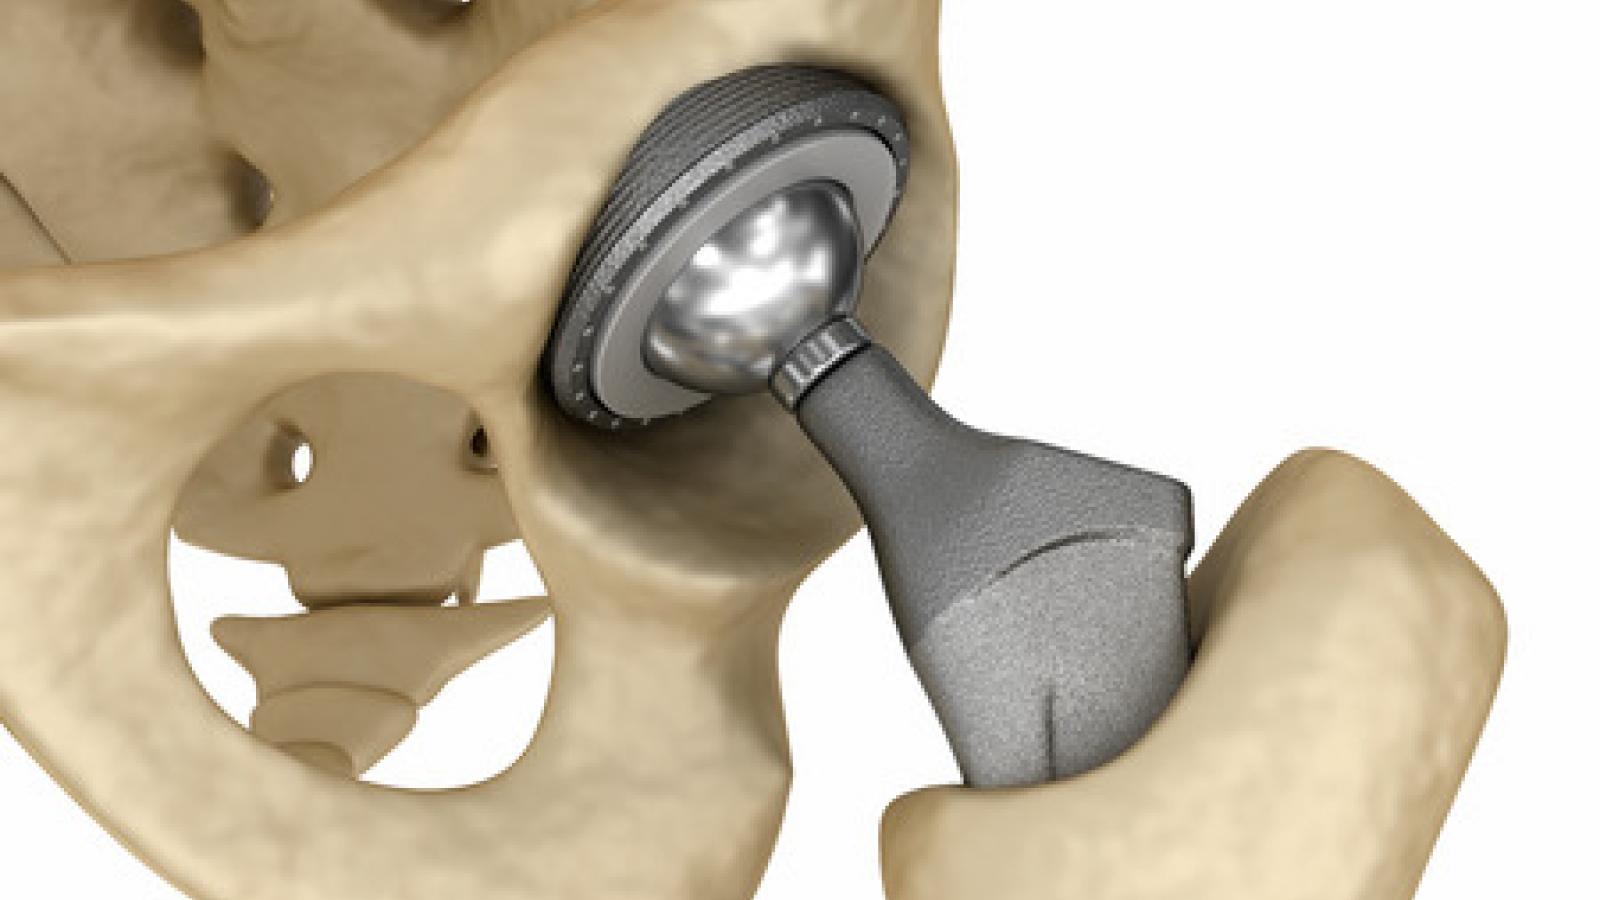

Замена таз сустава

Замена таз сустава 113 фотографий